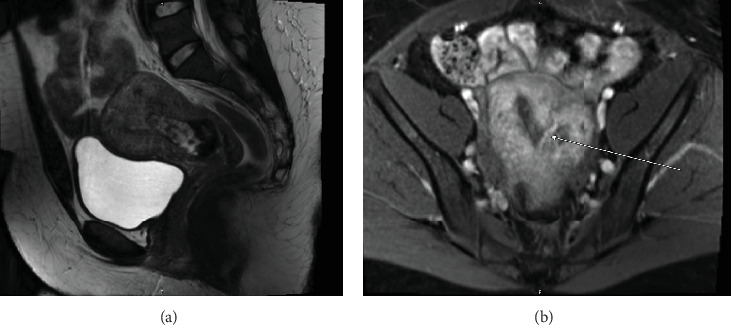

A placental polyp is a retained fragment of placental tissue that can lead to postpartum hemorrhage or become a nidus for infection. Hypervascular placental polyps can pose an increased risk of life-threatening postpartum hemorrhage requiring immediate intervention. Thus, prompt recognition and appropriate management are crucial in preventing maternal morbidity and mortality. Here, we present the case of a 29-year-old patient who had a spontaneous vaginal delivery at 36-week gestation after induction of labor due to pre-eclampsia with severe features. Quantitative blood loss at delivery was 1300 mL, and the patient received uterotonic medications. Due to continued bleeding, she underwent a suction curettage with clots and retained tissue removed from the uterine fundus. The total blood loss was estimated to be 4 L, and the massive transfusion protocol was activated. On postpartum Day 1, she underwent a bilateral uterine artery embolization; however, she developed further heavy vaginal bleeding. A second suction curettage was performed after ultrasound showed hypervascular material in the uterine cavity. The patient was subsequently discharged, but represented on postpartum Day 15 with increased bleeding. Imaging again demonstrated a hypervascular intrauterine polypoid mass. The patient desired definitive management and underwent a minimally invasive total hysterectomy.

胎盘息肉是残留的胎盘组织碎片,可导致产后出血或成为感染病灶。胎盘高血管性息肉可增加危及生命的产后出血的风险,需要立即干预。因此,及时认识和适当管理对于预防产妇发病率和死亡率至关重要。在这里,我们提出的情况下,29岁的病人有自然阴道分娩在36周妊娠引产后,由于先兆子痫严重的特点。分娩时定量失血量1300 mL,给予子宫强直药物治疗。由于持续出血,她接受了从子宫底取出血块和残留组织的抽吸刮除术。总失血量估计为4l,并启动了大量输血方案。产后第1天,她接受了双侧子宫动脉栓塞术;然而,她进一步出现大量阴道出血。超声显示子宫腔内有高血管物质后,行第二次吸刮术。患者随后出院,但产后第15天表现为出血增加。影像学再次显示一个高血管的子宫内息肉样肿块。患者希望得到明确的治疗,并接受了微创全子宫切除术。